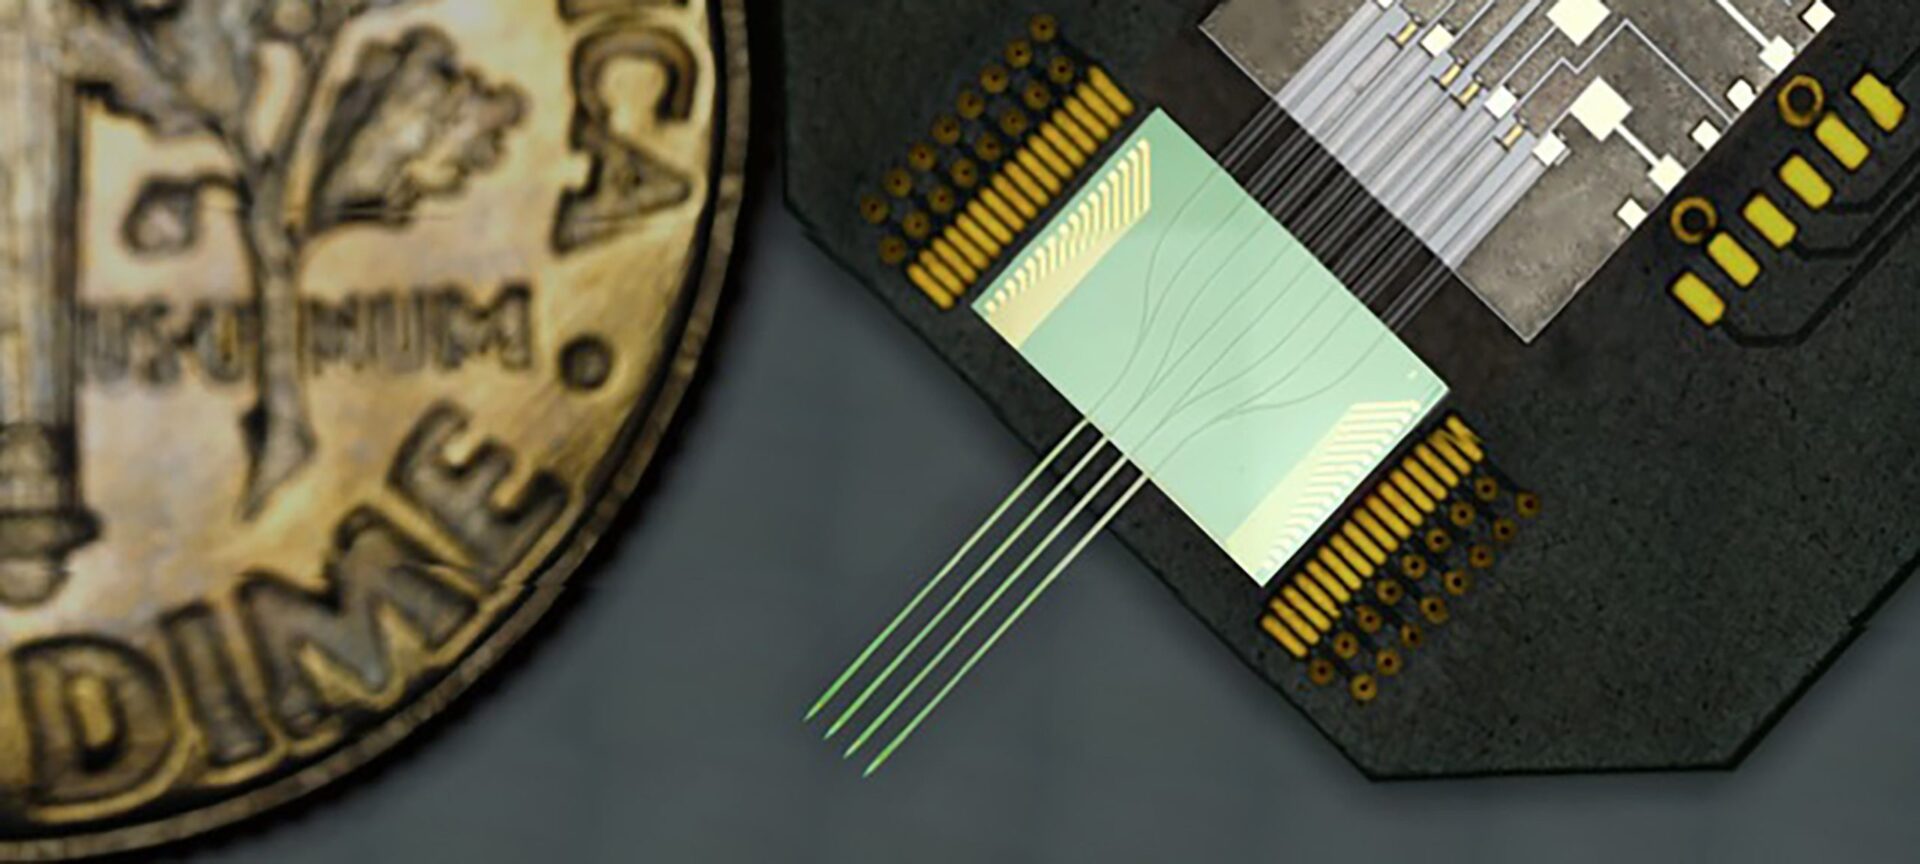

The Michigan Probe: Changing the Course of Brain Research

Some believed early Michigan brain researchers were engaging in “science fiction” – until development of an advanced tool for forging breakthroughs proved them wrong.

The post The Michigan Probe: Changing the Course of Brain Research appeared first on Michigan Engineering News.

Improved neural probe can pose precise questions without losing parts of the answers

It will now be possible to study brain activity when timing is important, such as the consolidation of memory.

Research on neural probe that sheds multicolor light on the complexities of the brain recognized for its impact

Prof. Euisik Yoon and his team are recognized for their work designing low-noise, multisite/multicolor optoelectrodes that will help neurologists learn more about neural connectivity in the brain.